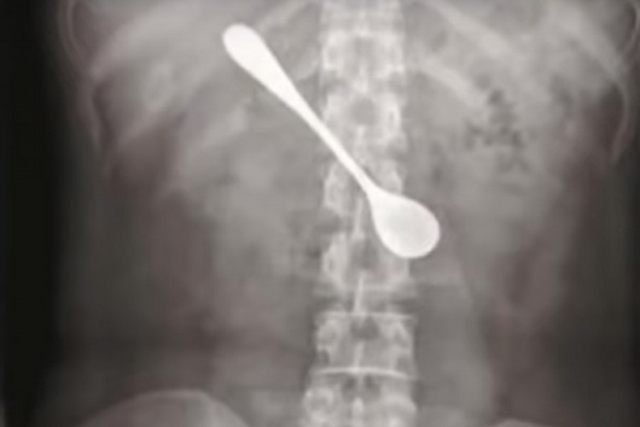

Pacijentkinja Lili progutala je kašiku dužine 13 cm. Prošlo je četiri dana pre nego što je potražila lekarsku pomoć, jer pre toga nije osećala nikakvu bol i nelagodu, prenose kineski mediji.

Nakon rendgenskog snimanja i edndoskopije, doktori su uspeli da joj izvade kašiku iz tela.